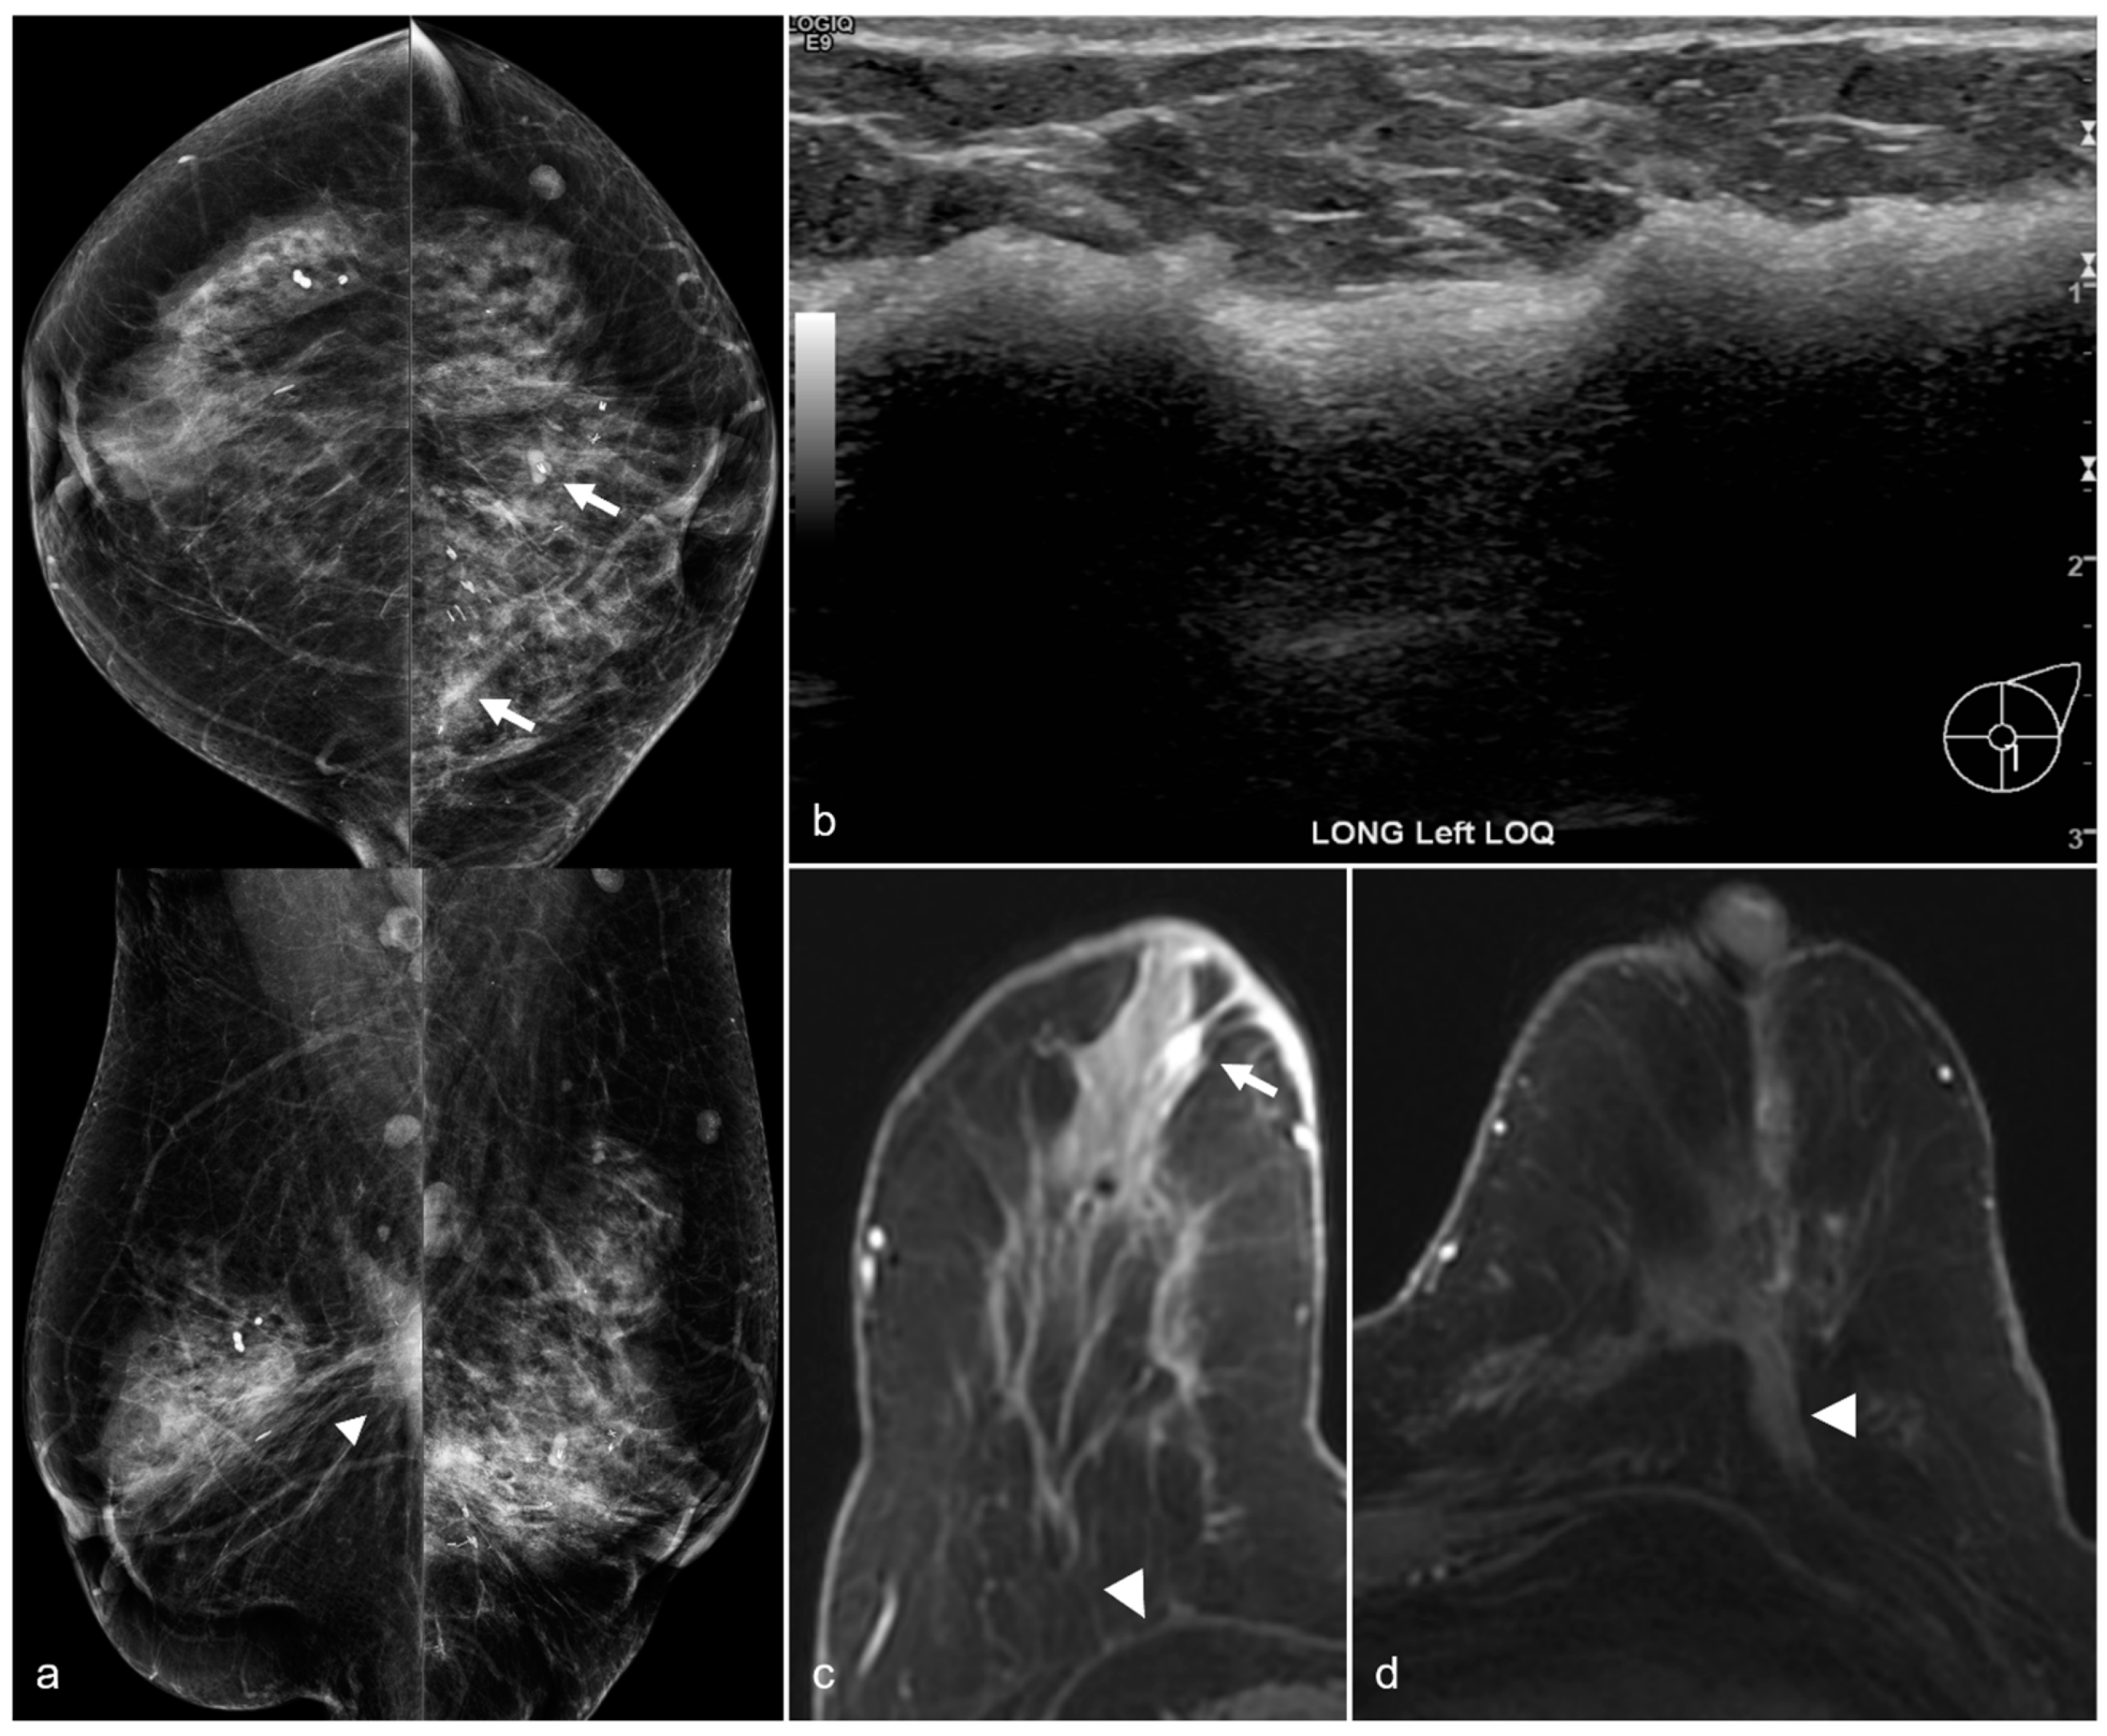

Figure 14. A 65-year-old woman with a history of a ruptured subglandular silicone implant. Screening mammogram (a) demonstrates very dense masses (arrows) in the left prepectoral region on the CC and the MLO views. Suspicious right breast calcifications (arrowhead) were biopsied with a biopsy clip seen in a hematoma in the right prepectoral region on the CC and MLO views. Pathology revealed ductal carcinoma in-situ. An additional biopsy was performed in the right breast for a small focal asymmetry (*) better seen on magnified CC view (b) and pathology demonstrated invasive ductal carcinoma. MRI demonstrates a T1 isointense peripherally enhancing silicone granuloma in the left breast prepectoral region ((c), arrows). In the right breast, a biopsy clip is seen within the biopsy cavity ((d), arrowhead). Anterior and inferior to this region (e), there is a linear non-mass enhancement. More anterior and medial to the non-mass enhancement, there is an enhancing mass (*), corresponding to the biopsy-proven invasive ductal carcinoma.